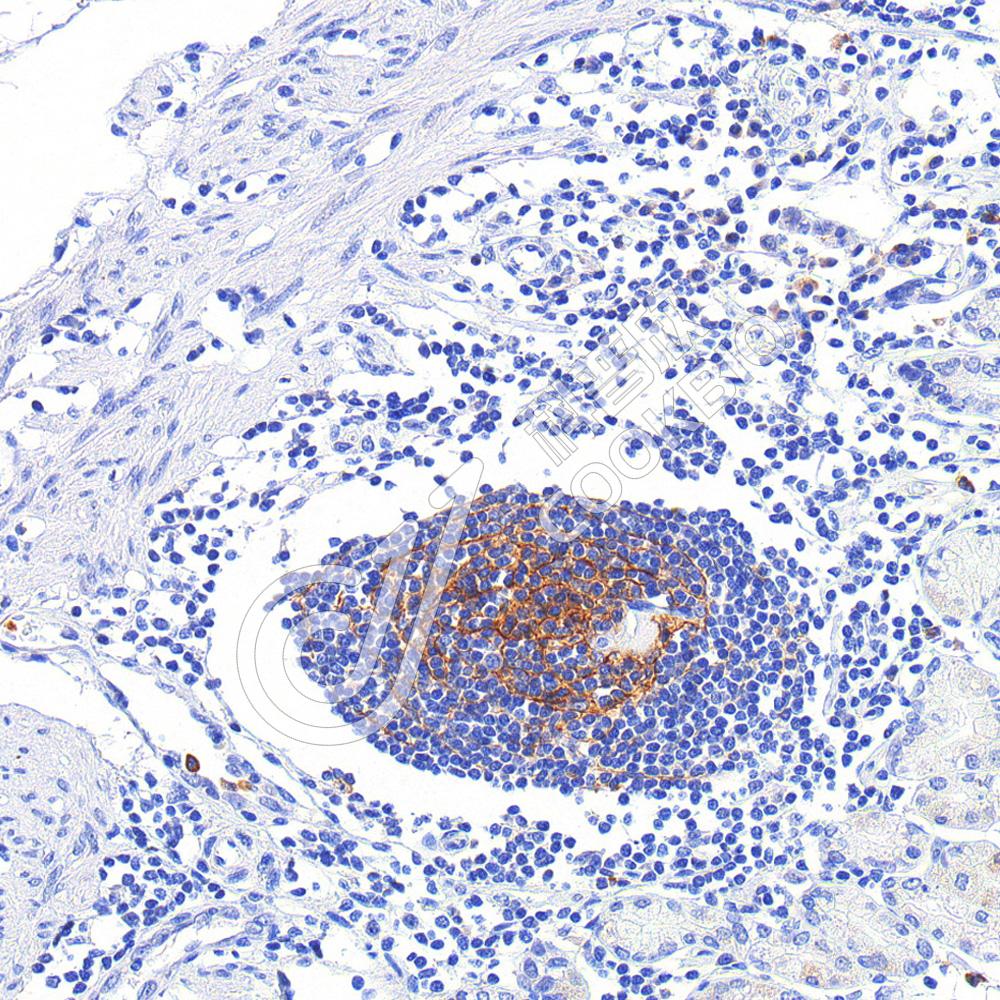

IHC检测CD11b蛋白(货号 K2377079).

样品: 人肝癌, 4%多聚甲醛 (货号KSG1101) 固定12-24小时.

抗原修复: 柠檬酸抗原修复液(干粉, pH 6.0) (KSG1201), 高压锅均匀喷气计时2分钟.

—抗: 1: 1000稀释, 4℃ 孵育过夜.

二抗: S-vision免疫组化多聚二抗(山羊抗小鼠), 即用型(货号KB3903), 室温孵育20分钟.

样品: 人胃癌, 4%多聚甲醛 (货号KSG1101) 固定12-24小时.